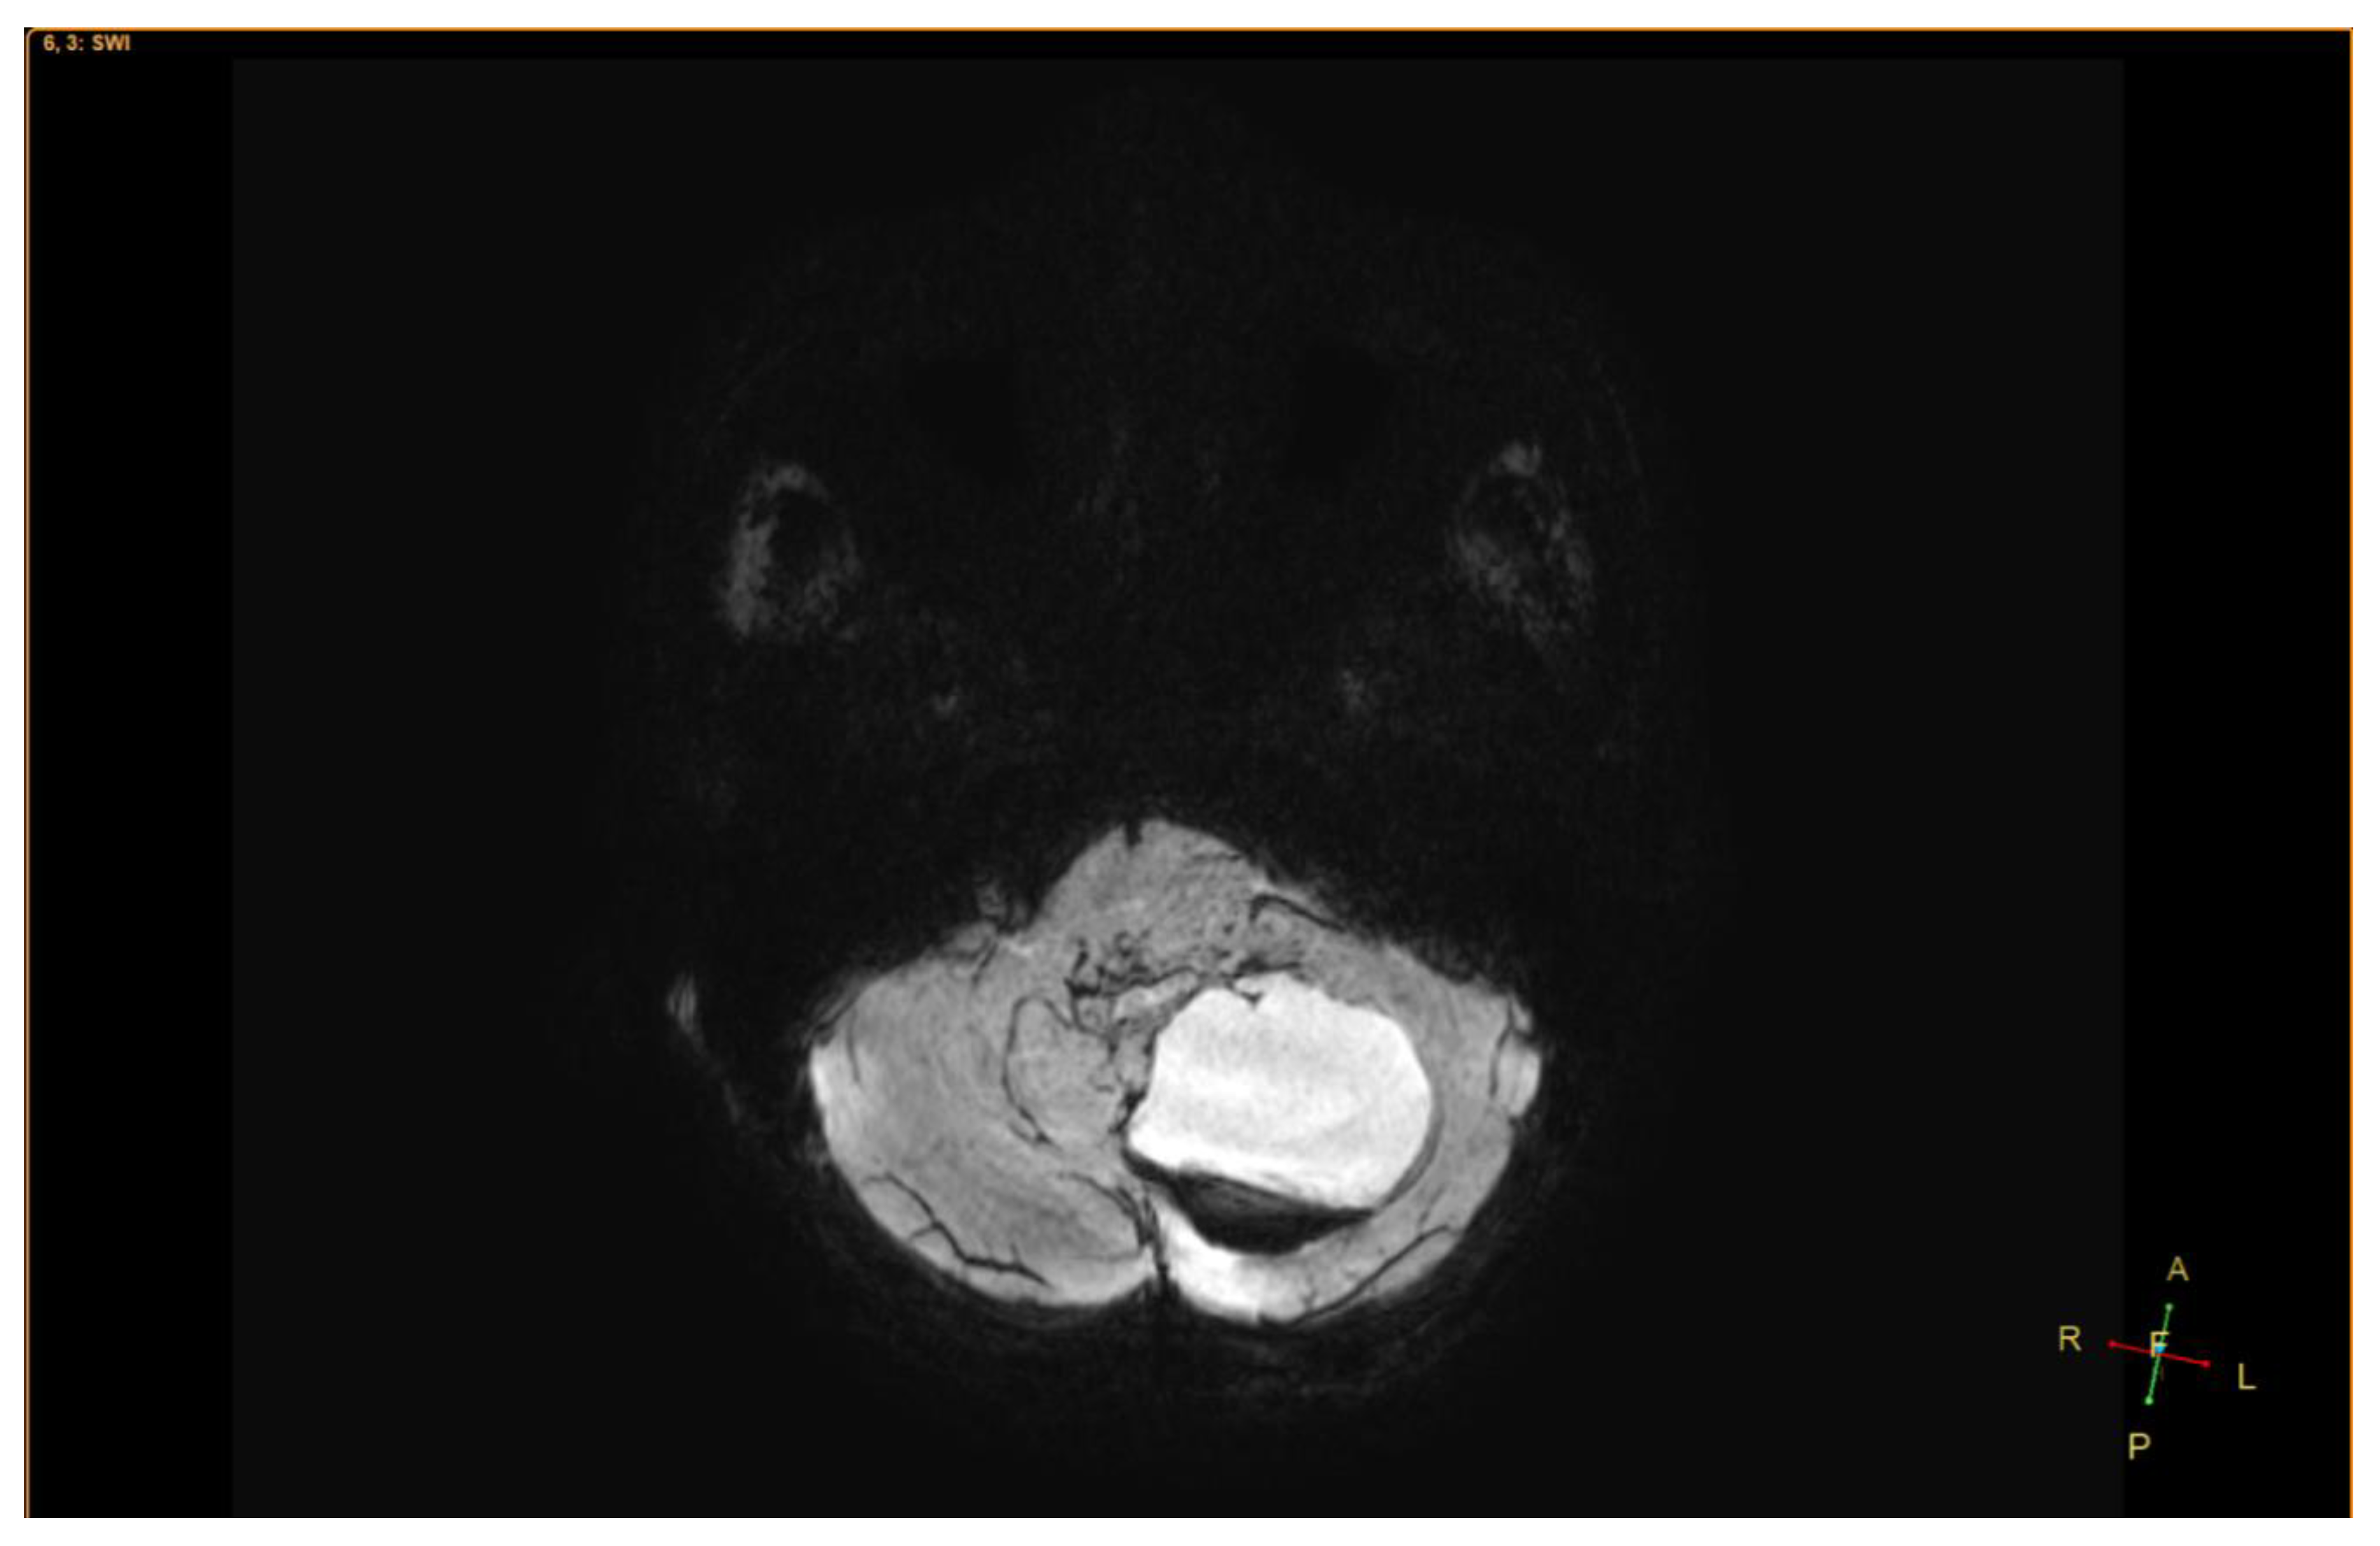

2. Case Presentation